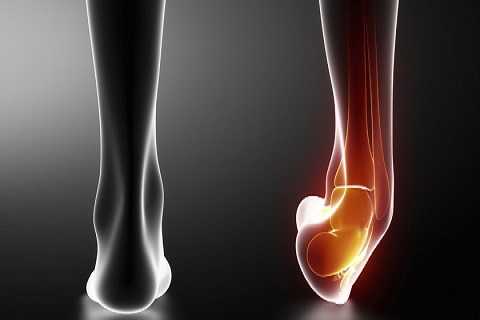

Esguinces de ligamentos

Un esguince es un estiramiento o desgarro de los ligamentos, las bandas resistentes de tejido fibroso que conectan dos huesos en las articulaciones.